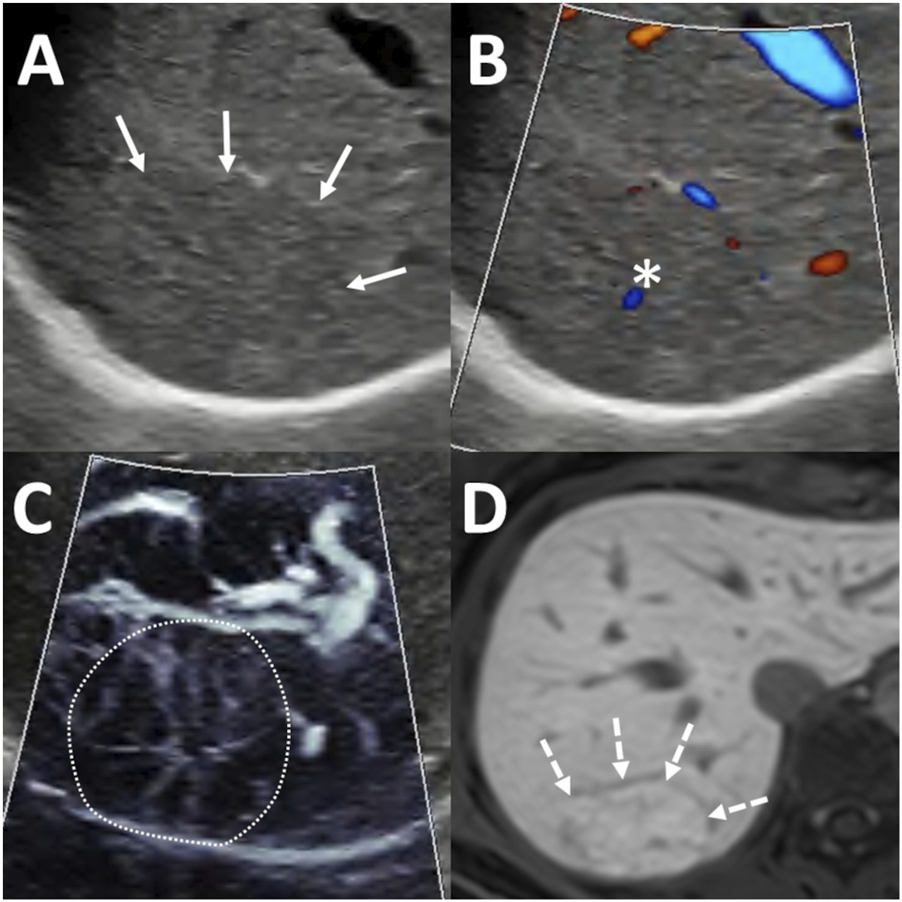

FIGURE 3

Diagnosis of focal nodular hyperplasia (FNH) using ultrasound (US) and magnetic resonance imaging (MRI). A 65 mm lesion was located beneath the diaphragm in segment 7 (A) Greyscale US showed an isoechoic lesion with indistinct margins (arrows). (B) Color-coded power Doppler imaging (PDI) highlighted the flow signal in a central artery (asterisk). (C) Microvascular imaging (MVFI) revealed a spoke-wheel vascular pattern within the lesion (outlined by the dotted line). (D) On hepatobiliary phase MRI, the lesion appeared hyperintense (dashed arrows) relative to the surrounding liver parenchyma, with a hypoenhancing central scar also visible.

The presence of a central artery on MVFI was found to be a characteristic feature of FNH according to the first observer (OR = 4.96; 95% CI: 1.19–23.00; p < 0.03), but this association was not statistically significant for the second observer (OR = 1.85; 95% CI: 0.45–7.10; p = 0.373). The first observer identified a central artery in 30 FNH lesions (73%), as well as in 4 HCCs (19%), 3 METs (15%), and 2 HCAs (20%) (Figure 3). In comparison, the second observer detected a central artery in 32 FNHs (78%), 8 HCCs (38%), 6 METs (30%), and 3 HCAs (30%).